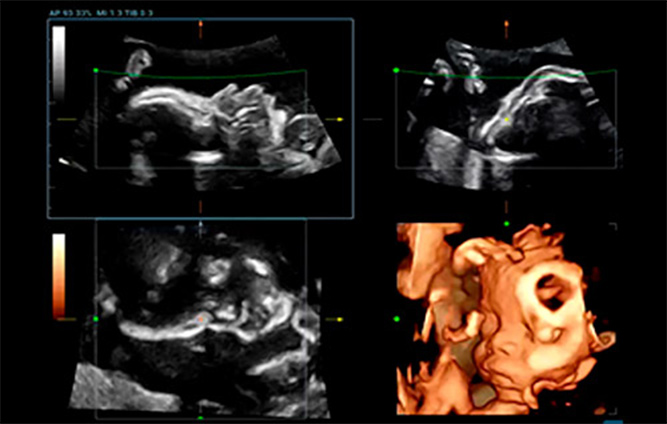

Smart Face